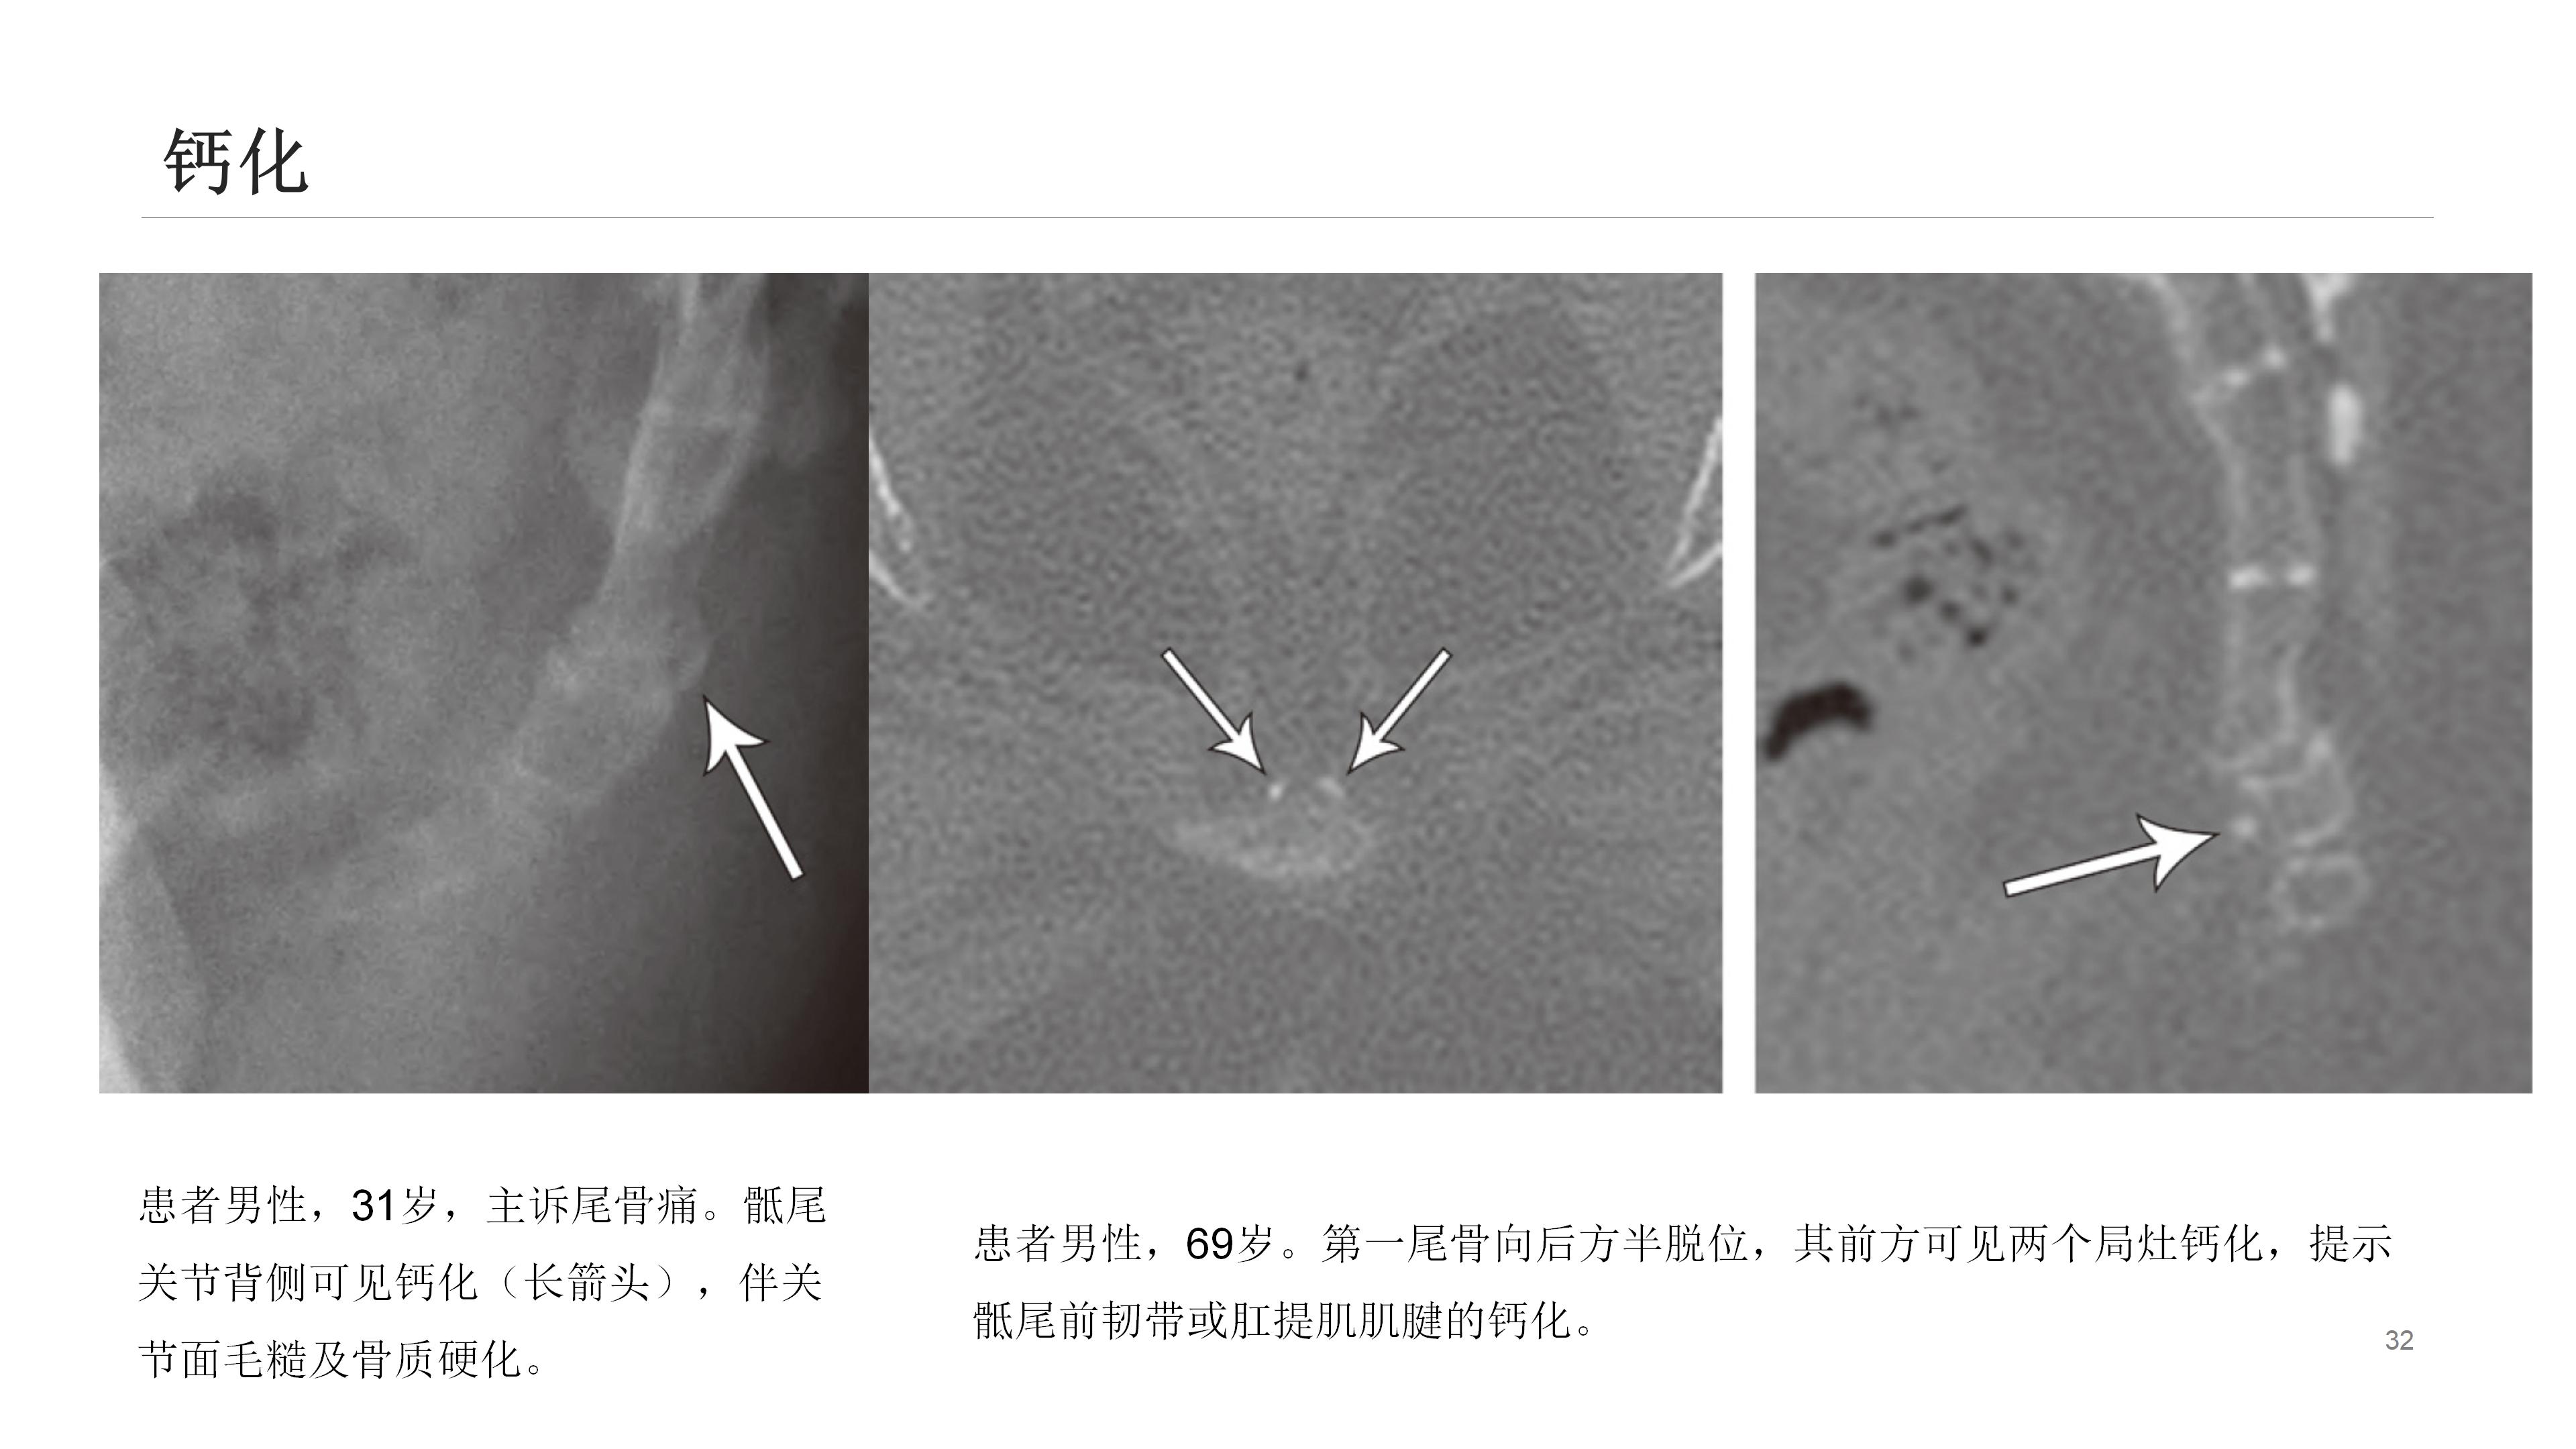

尾骨区域解剖结构复杂,众多结构皆可能引发该区域疼痛。影像学能出色呈现其解剖学特点,辨别受累结构可指导临床处置。尾骨疼痛乃常见临床症状,却难以评估和治疗。

通常,尾骨疼痛多在创伤后出现,初始静态平片检查可能正常,而动态平片(站立位及坐侧位平片)或可观察到异常尾骨移动,以此解释疼痛来源。

此外,诸如肿瘤、感染、晶体沉积病、囊肿形成(如藏毛囊肿)等其他疾病也可导致尾骨疼痛。